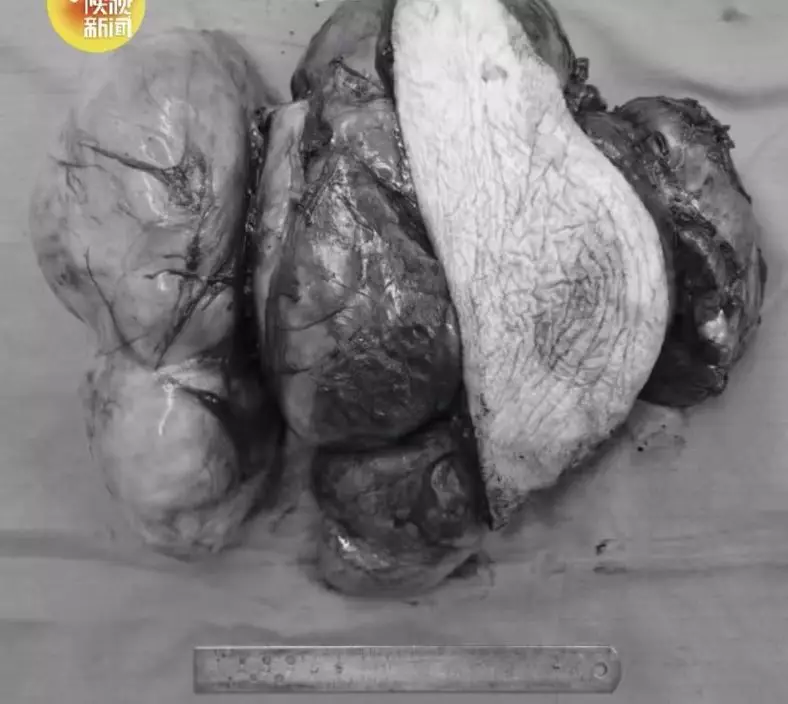

陝西9旬老翁肩扛巨瘤逾10年,皮膚一度險被撐破,過去因高齡及手術風險高多次被拒治療。近日,他終於接受2小時手術成功切除腫瘤,卸下多年沉重負擔。

9旬老翁肩扛巨瘤逾10年,皮膚一度險被撐破。影片截圖

綜合內媒報導,陝西西安一名95歲老翁肩上長出巨大腫瘤,10多年來一直壓在左肩及上臂位置。近年來,腫瘤急速增大,幾乎要將肩部皮膚撐破,疼痛也明顯加劇。老翁曾到多地求醫,但因年紀太大、手術風險高,多次被婉拒治療。直至今年4月,他到空軍軍醫大學唐都醫院骨科求診,醫生評估後決定為他進行手術,最終成功完整切除腫瘤,幫助老翁卸下長達10多年的「沉重負擔」。

9旬老翁肩扛巨瘤逾10年,皮膚一度險被撐破。影片截圖

腫瘤急速變大 幾乎環繞上臂四分之三

報導指出,患者馮大爺今年95歲,左肩及左上臂位置的腫瘤已存在逾10年。起初腫瘤增長較慢,但近年突然快速變大,幾乎環繞上臂四分之三,肩部皮膚被撐得非常薄,甚至接近破裂,並伴隨明顯痛楚,嚴重影響日常生活。

9旬老翁肩扛巨瘤逾10年,皮膚一度險被撐破。影片截圖

高齡手術風險大 醫生判斷為脂肪肉瘤

由於馮大爺年事已高,手術過程可能面臨大出血、器官功能衰竭等風險,因此此前多間醫院均認為風險過高,未有為他進行手術。家人之後帶他到空軍軍醫大學唐都醫院骨科就診,醫生經檢查後判斷,肩部巨大腫物為「脂肪肉瘤」。

2小時手術完整切除 多年負重終於解除

唐都醫院骨科團隊隨即為馮大爺制定手術方案,經過約2小時手術,醫生成功將這個幾乎包圍上臂四分之三的巨大腫瘤完整切除,並在手術過程中盡量避開重要血管及神經。手術後,馮大爺肩頭多年的負重終於解除,恢復情況良好。

9旬老翁肩扛巨瘤逾10年,皮膚一度險被撐破。影片截圖